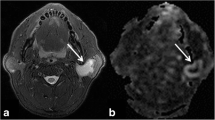

Figures 1, 2, and 3 show representative cases of MTs, PAs, and WTs, respectively. Supplementary Table S1 shows the results of Shapiro–Wilk test for each parameter. Tables 2 and 3 show the parameter measurements of TBF and ADC, respectively, in MTs, PAs, and WTs.

An 83-year-old male patient with a Warthin’s tumor in the left parotid gland. T2-weighted image (a) showing iso signal intensity lesion (arrow). Contrast-enhanced 3D-T1-weighted image (b) showing homogeneous contrast enhancement (arrow). Tumor blood flow (TBF) color map (c) showing high TBF (arrow). The region of interest (ROI) was manually drawn on the apparent diffusion coefficient (ADC) map of the software (e, yellow), and the ROI was copied from the ADC map to the TBF map of the software (d, yellow). TBF histogram (f) and ADC histogram (g) are presented. The 50th percentile of the TBF value was 117.90 mL/100 g/min, whereas the 10th percentile of ADC value was 0.53 × 10−3 mm2/s.